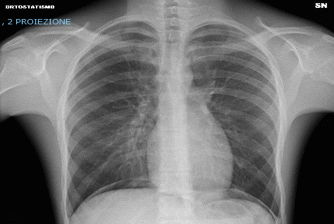

Venivano, quindi, eseguiti radiografia del torace (Figura 1), con evidenza di “importante grado di interstiziopatia da verosimile stasi del piccolo circolo”, broncolavaggio alveolare, mostrante “tappeto di granulociti e macrofagi alveolari su terreno ematico” e TC del torace, accertante “plurime opacità da impegno alveolare che interessano in modo ubiquitario i lobi polmonari”; si giungeva dunque a diagnosi di alveolite emorragica, non attribuibile a cause infettive, autoimmuni e farmacologiche, stante la negatività degli esami specifici effettuati. A una anamnesi più approfondita emergeva, invece, uso frequente di Cannabis naturale nel mese precedente all’intervento, sia sotto forma di “bongo” che di sigaretta (circa 1-2 al giorno), ciò confermato dall’esito positivo dell’esame tossicologico urinario.

Figura 1. Rx torace: importante interstiziopatia da verosimile stasi del piccolo circolo, compatibile con emorragia alveolare diffusa.